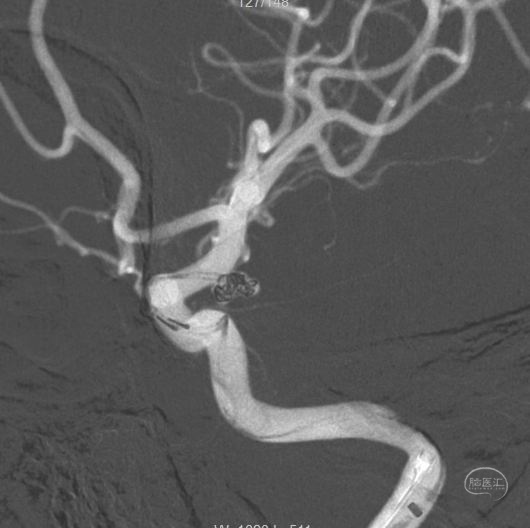

术后工作位造影

换角度观察,栓塞满意。

正位